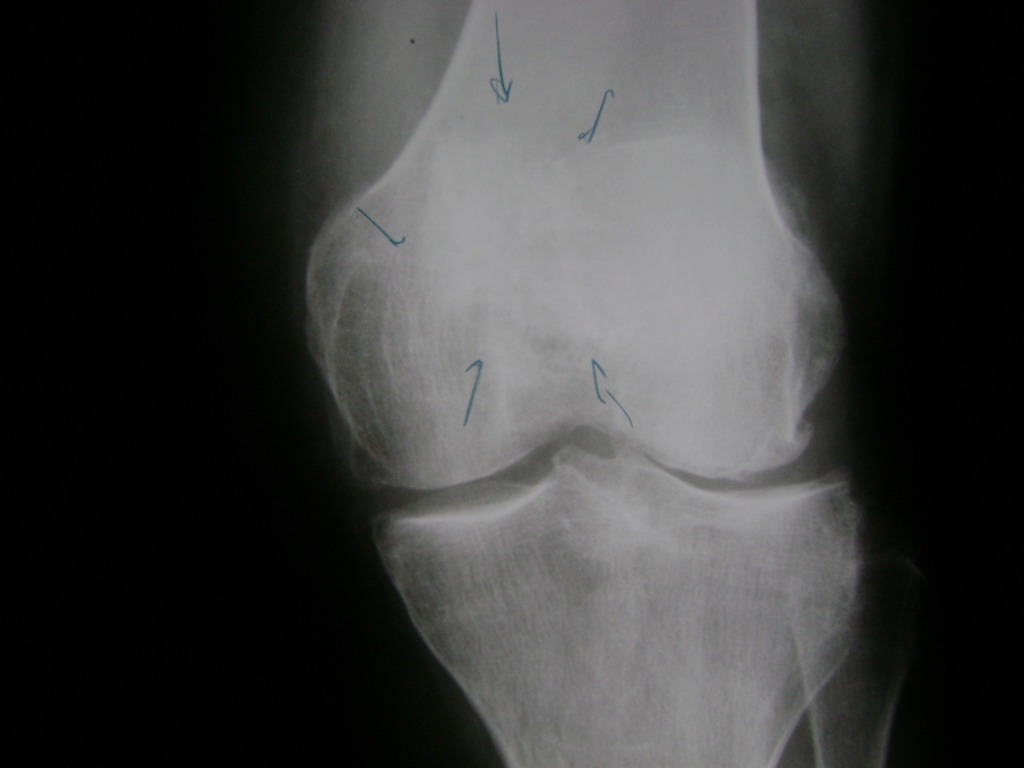

Fémur - Rodilla

La artroscopia de rodilla es un cirugía en el cual la estructura interna de la articulación es examinada ya sea para realizar un diagnostico o para realizar un tratamiento, este procedimiento se realiza utilizando un instrumento parecido a un pequeño tubo llamado artroscopio.